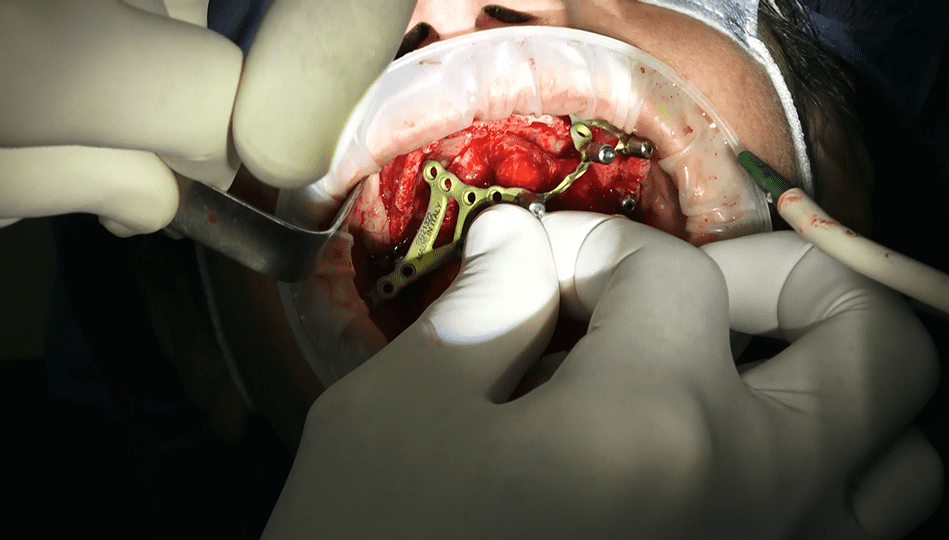

• Griglia e Viti di Osteosintesi: Viene utilizzata una griglia con viti di osteosintesi per fissare gli impianti e garantire una stabilità ottimale nella mascella o nella mandibola scheletrizzata.

• Il video documenta ogni fase dell’intervento, dalla progettazione personalizzata della griglia sottoperiostea all’applicazione dei singoli impianti e, infine, alla realizzazione di una protesi dentale a carico immediato.

• Durante l’intervento chirurgico, la griglia sottoperiostea viene posizionata direttamente sull’osso mascellare, fornendo un supporto stabile per gli impianti dentali.